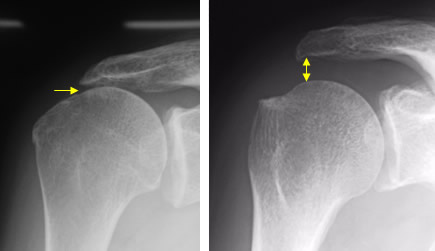

エックス線検査

単純レントゲンは基本的な検査です。エックス線では腱板を見ることはできませんが、肩峰に骨の棘、関節の隙間で狭くなっていることを認めることがあります。

骨のとげ

年齢とともに肩峰に骨の棘が大きくなります。腕を持ち上げたときに骨棘と腱板が衝突することを、インピンジメント現象と呼んでいます。インピンジメント現象を繰り返していると腱板断裂の危険があり、場合によっては骨棘を切除することがあります。